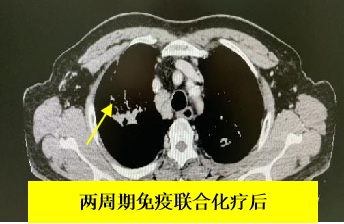

在完成兩周期「免疫藥物+化療治療」後,老秦的腫瘤縮小到了較為理想的範圍。

老秦如期接受了根治性手術(shù)治療。馬鍇教授帶領(lǐng)胸外科團隊,操作達文西機械人手術(shù)系統(tǒng),精細化地撥開血管,一點點地將腫瘤與肺動脈、支氣管分離。手術(shù)過程堪稱「肺動脈邊上走鋼絲」,在保證切乾淨腫瘤的同時,還要避免損傷肺動脈。按10分難度評級,馬鍇教授給這臺手術(shù)的打分是8-9分。